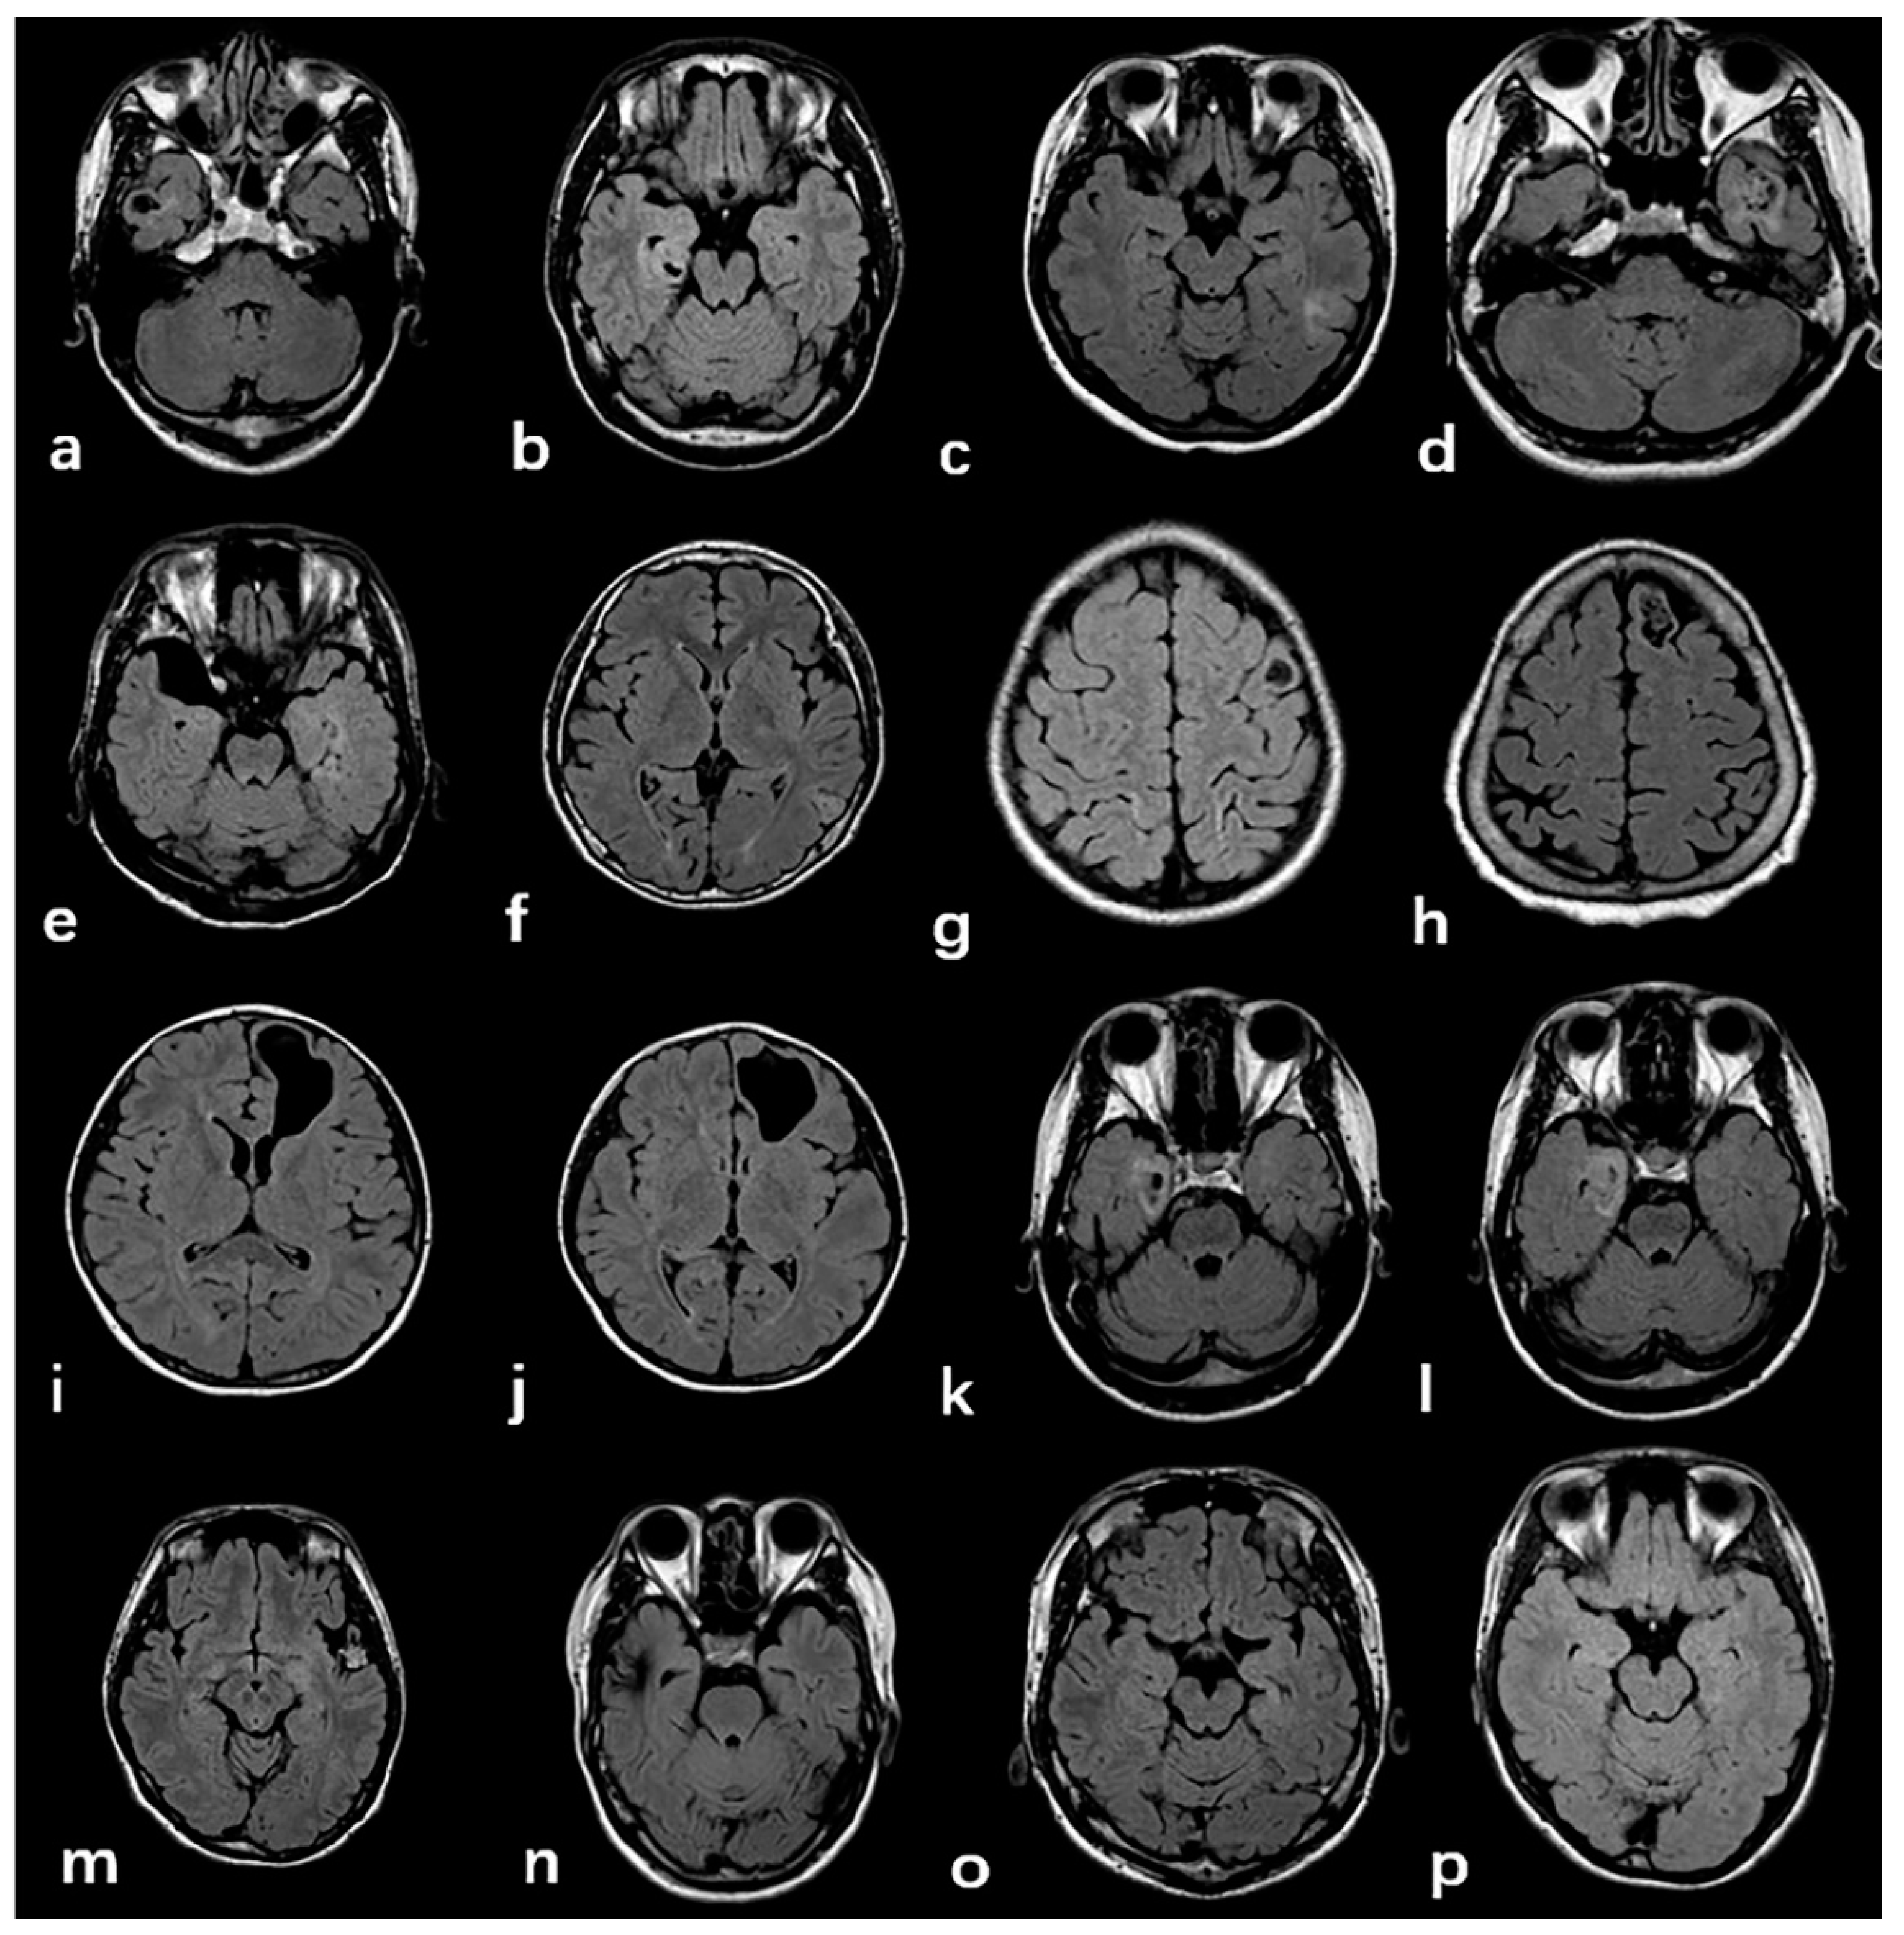

3.2. Radiologic and Pathology Findings

| MRI features of FCD | 0.680 | |||

| Cortex atrophy/thickening | 90 (13.5%) | 59 (13.4%) | 31 (13.8%) | |

| Indistinctness of the gray–white matter junction | 176 (66.2%) | 118(65.9%) | 58 (66.7%) | 1.000 |

| Intensity | 166 (62.4%) | 116 (64.8%) | 50 (57.5%) | 0.281 |

| MRI Negative | 36 (13.5%) | 19 (10.6%) | 17 (19.5%) | 0.056 |

| Total | FCD Subtype | FCD-Associated Tumor | |||||||||

| FCD IIIa | 183 | 15 (8.6%) | 147 (84.0%) | 13 (7.4%) | / | / | / | / | / | / | / |

| FCD IIIb | 61 | 5 (8.6%) | 49 (84.5%) | 4 (6.9%) | 41 (67.2%) | 14 (22.9%) | 1 (1.6%) | 1 (1.6%) | 1 (1.6%) | / | / |

| FCD IIIc | 22 | 1 (4.5%) | 21 (95.5%) | 0 | / | / | / | / | / | 15 (68.2%) | 7 (31.8%) |